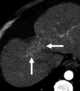

Confluent fibrosis